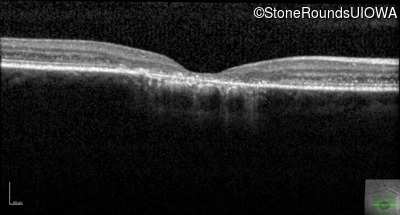

Optical Coherence Tomography - Left - 20/80 -2 sc

Exemplar / OCT Stack